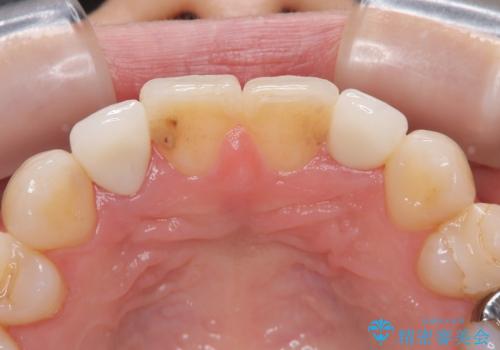

根管治療をしているため、歯の変色が認められます。

特に症状はなく、根管治療のやり直しは希望されなかったため、土台のやり替えから処置をしていくとととしました。

もともと矮小歯で歯の大きさが小さいことが気になっていましたが、改善されて満足されました。